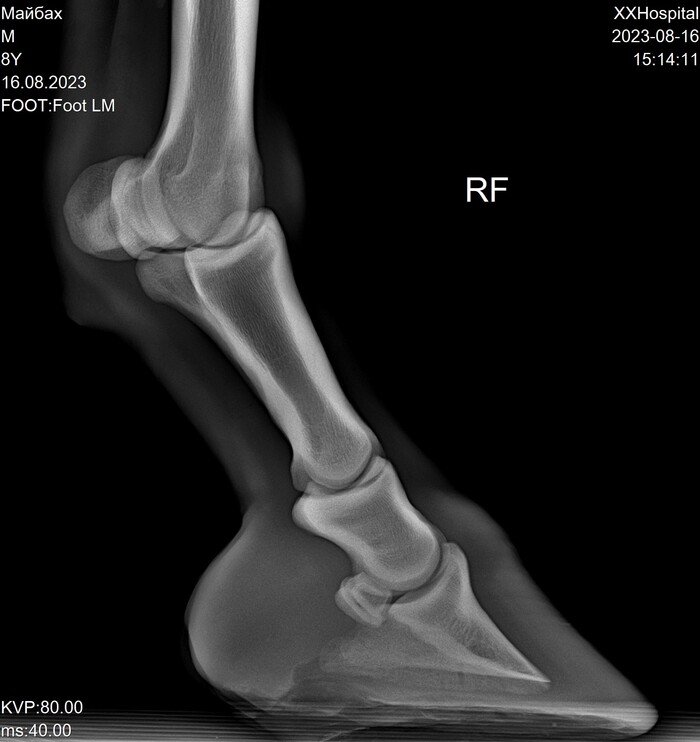

Пока лента далеко не убежала и есть возможность сравнить с идеальными снимками Майбаха (см. предыдущий мой пост , там комментировать нечего, всё круто).

На этих x-ray снимках Домбай.